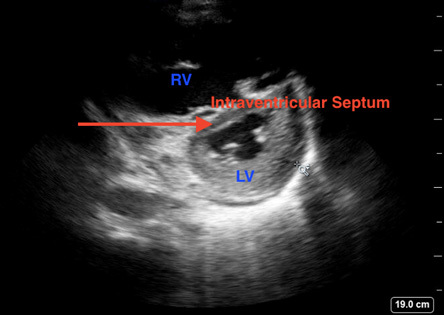

Figure 3. Septal Bowing Caused by Right Ventricular Strain Demonstrating Classic D Sign |

Point-of-care ultrasound image demonstrating a parasternal short view with septal bowing (red arrow) caused by right ventricular strain demonstrating classic “D sign” |